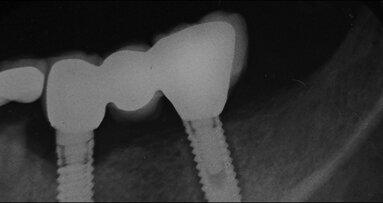

Obr. 3: Po opracování vestibulárních kořenů technikou step-back v intervalech 0,5 mm pomocí AS 30 až 40 a v palatinálním kořenu pomocí AS 40 na PD, rtg snímek během plnění (konec fáze preparace apikálním směrem, System B).

Obr. 4 a 5: Rtg snímek po výkonu v centrické (4) a excentrické (5) projekci (zaplnění: System B a termoplastická gutaperča).